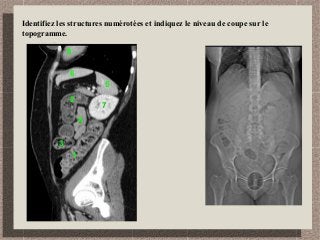

Identifiez les structures numérotées et indiquez le niveau de coupe sur le

topogramme.

1

2

3

4

5

6

7

8

1: côlon descendant

2: angle splénique

3:côlon transverse

4: jéjunum

5: rate

6: foie (segment 3)

7: rein gauche

8: coeur